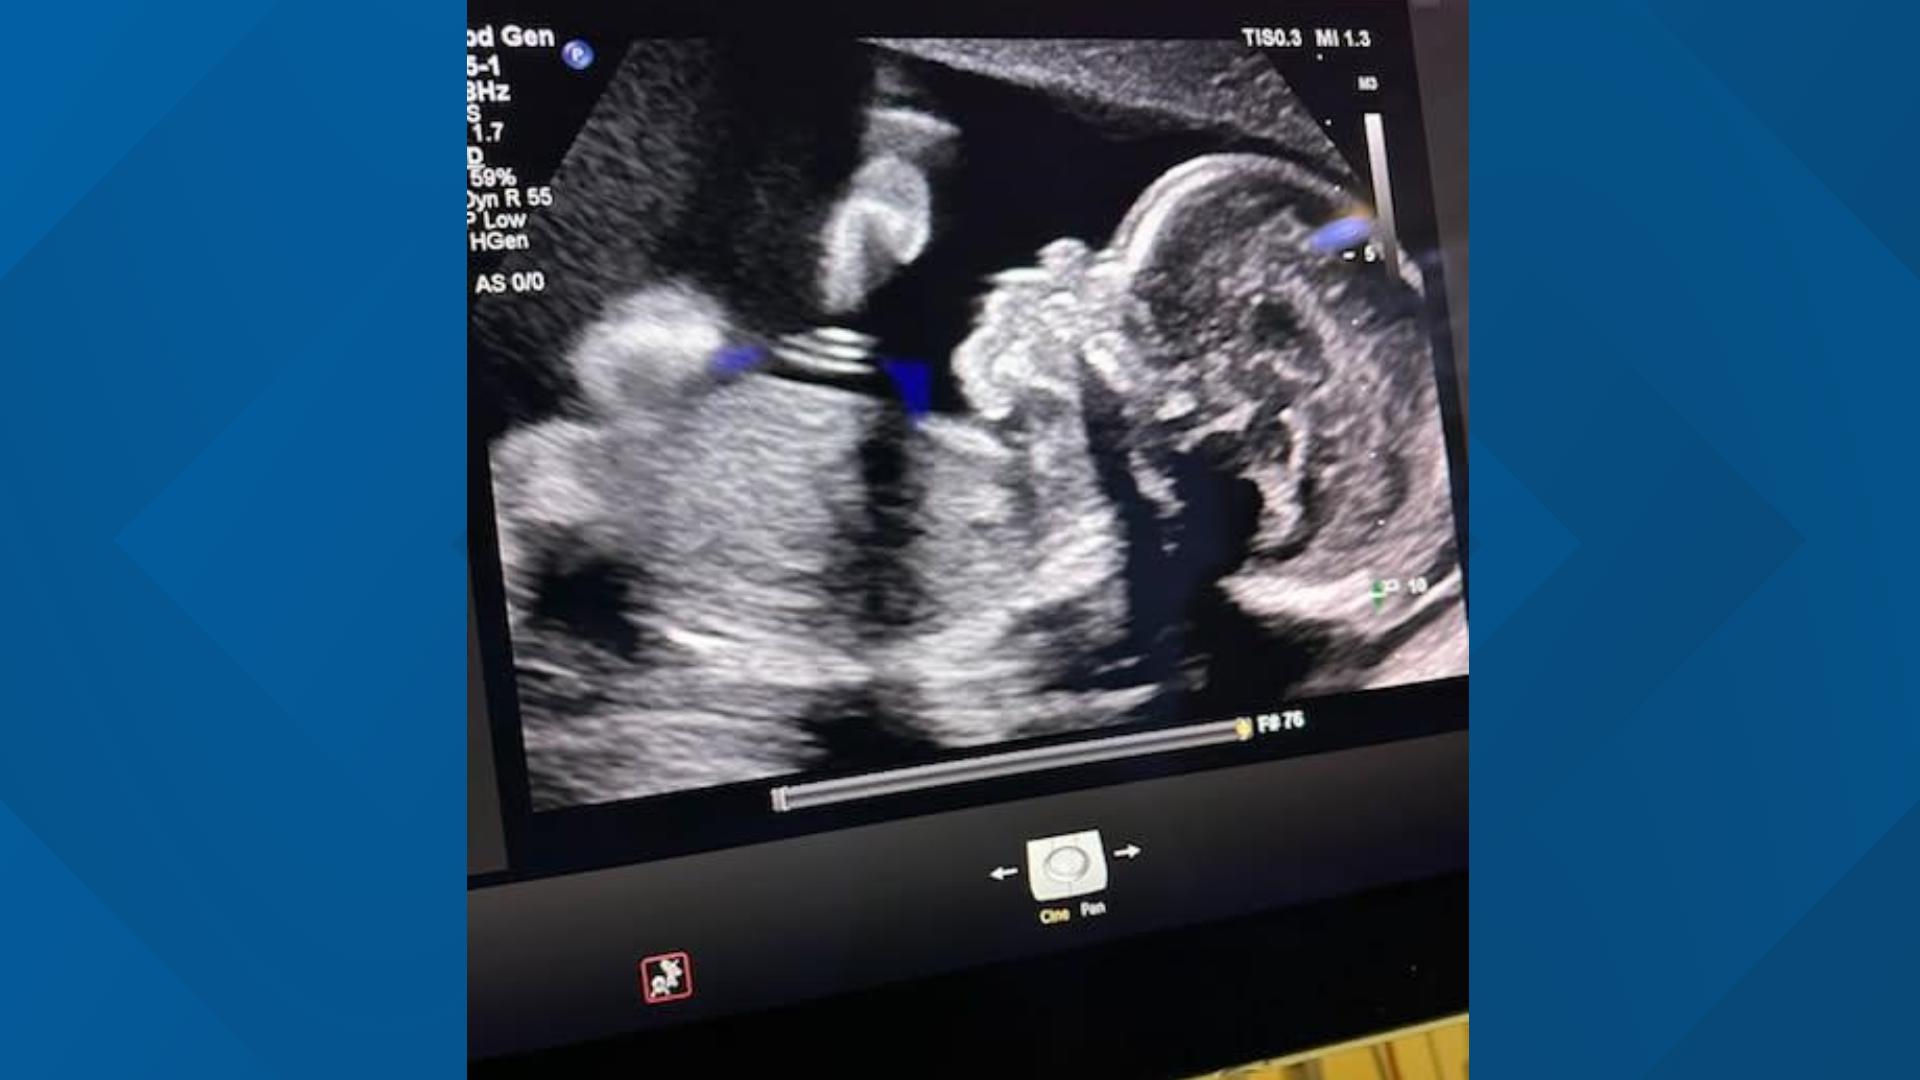

Adriana Smith’s Pregnancy Continues Without Consent - Adriana Smith Pregnancy News: Is She Expecting?

Adriana Smith: Family Forced to Keep Brain-Dead Daughter on Life - Adriana Smith Pregnancy News: Is She Expecting?

Pregnant Georgia mother on life support | Expert insight | 11alive.com - Adriana Smith Pregnancy News: Is She Expecting?

In the United States, it is known that a woman who has been brain-dead - Adriana Smith Pregnancy News: Is She Expecting?

Brain dead Georgia mom taken off life support after baby born | 11alive.com - Adriana Smith Pregnancy News: Is She Expecting?

Family claims woman declared brain dead but pregnancy continues due to - Adriana Smith Pregnancy News: Is She Expecting?

Adriana Smith’s Pregnancy and Georgia’s Brutal Abortion Law - Adriana Smith Pregnancy News: Is She Expecting?

Georgia mother says she is being forced to keep brain-dead pregnant - Adriana Smith Pregnancy News: Is She Expecting?

Pregnant Black Mom Declared Brain Dead 90 Days Ago, But Still on Life - Adriana Smith Pregnancy News: Is She Expecting?

Brain-dead pregnant woman's 'tissues rotting' as docs refuse to switch - Adriana Smith Pregnancy News: Is She Expecting?

'Heartbeat law' not keeping pregnant woman alive, AG insists - Adriana Smith Pregnancy News: Is She Expecting?

Adriana Smith and Georgia’s law regarding pregnant patients on life - Adriana Smith Pregnancy News: Is She Expecting?

Adriana Smith Is Brain Dead. Georgia Law Controls Her Pregnancy - Adriana Smith Pregnancy News: Is She Expecting?

Adriana Smith | TODAY.com - Adriana Smith Pregnancy News: Is She Expecting?

Brain dead pregnant woman kept alive in Georgia—and her son is now 22 - Adriana Smith Pregnancy News: Is She Expecting?

Mother Says Abortion Ban Is Forcing Her to Keep Brain-Dead Pregnant - Adriana Smith Pregnancy News: Is She Expecting?